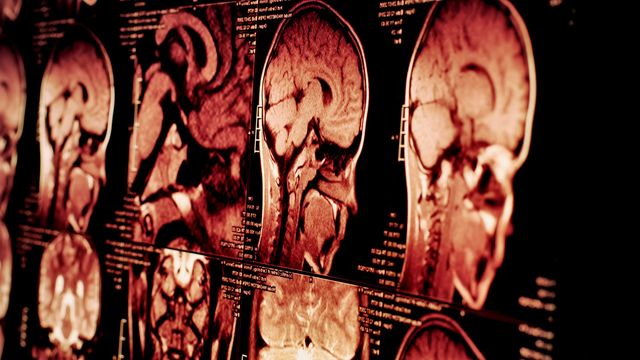

Psychosis May Share a Common Dopamine Link Across Diagnoses

A UK brain imaging study found that dopamine changes are linked to psychotic symptoms in people with schizophrenia, bipolar disorder or depression. PET scans showed shared and distinct dopamine patterns across diagnoses.